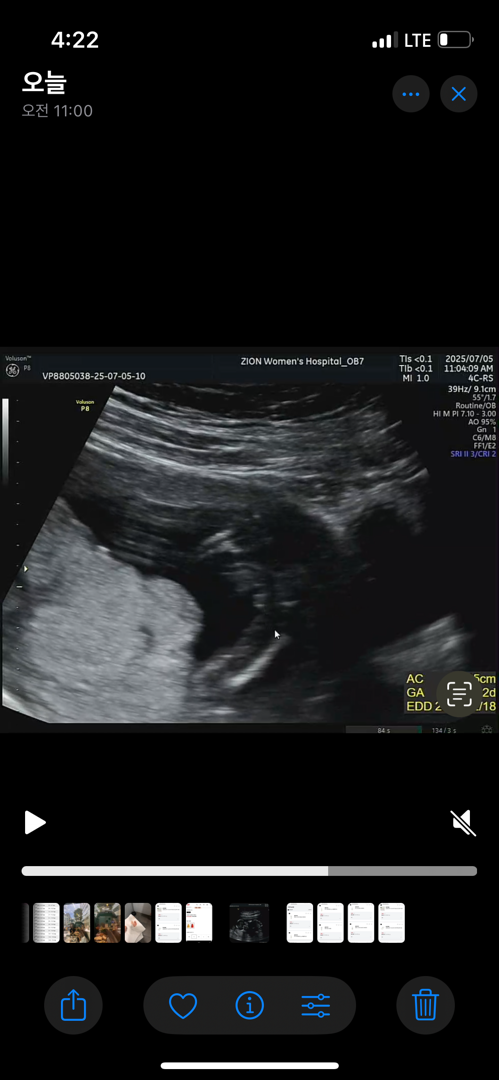

16주 성별문의

병원다녀왔어요 오늘! 아기가 책상에 앉은 자세 하고 있어서… ㅜ 교수님은 정확하진 않은데 딸같다고 하긴 했는데 한번 봐주세요!! 제발 성별반전없이 딸이었으묜…!!